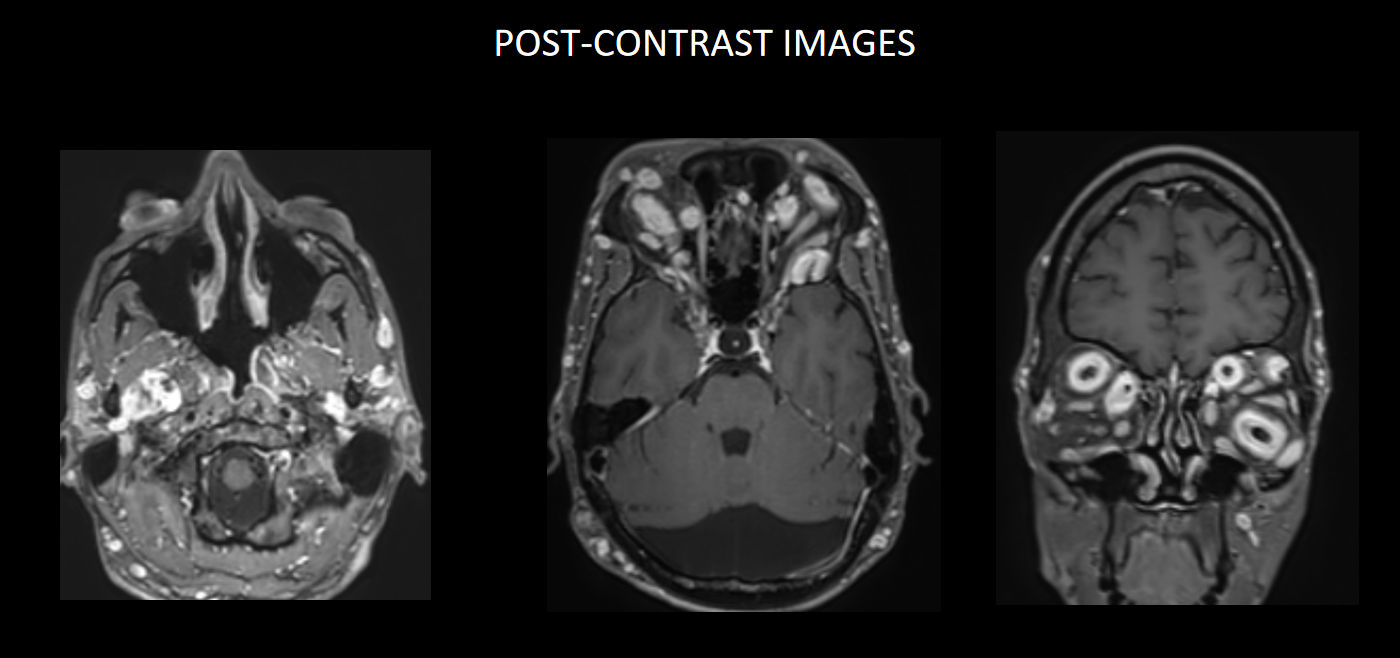

FINDINGS – MRI BRAIN WITH IV CONTRAST

Multinodular T2 hyperintense hypointense transpatial lesions seen within the bilateral orbits occupying the intra and extraconal spaces with targetoid appearance.

The lesion extends through the inferior orbital fissure into the pterygopalatine fossa bilaterally.

The lesions also extend through the foramen ovale into the superior aspect of masticator space bilaterally.

Similar heterogeneously enhancing nodular lesions are also seen bilateral fronto-temporal and occipital scalp regions. Incidental retrocerebellar arachnoid cyst.

Lesion extends into the orbital apex and along the bilateral cavernous sinuses.

Similar heterogeneously enhancing nodular lesions are seen extending into the upper neck in bilateral parotid and the visualised level II regions.

The lesions show heterogenous post-contrast enhancement.

They are best visualised on fat suppressed T2 weighted MR imaging where they appear as hyperintense masses with or without multiple target signs.

They demonstrate mild enhancement with IV gadolinium and are isointense on T1 signal.